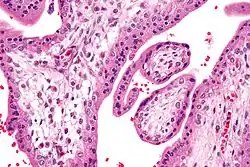

Hofbauer cells are oval eosinophilic histiocytes[1] with granules and vacuoles found in the placenta, which are of mesenchymal origin, in mesoderm of the chorionic villi, particularly numerous in early pregnancy.

Under histology sections, Hofbauer cells have appeared with discernible amount of cytoplasm.